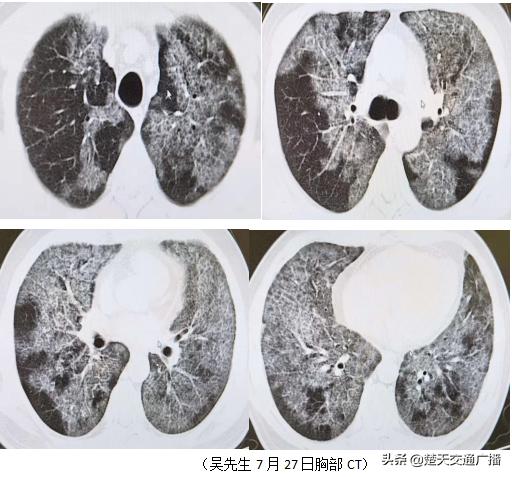

56岁的吴先生平素体健,半年前开始出现晨起时咳嗽,咳少量黄白色粘痰,伴有活动后喘气、胸闷,未予处理,喘气、胸闷症状逐渐加重,影响日常生活。7月底,吴先生到泰康同济(武汉)医院健康管理中心体检,胸部CT检查提示双肺弥漫性间质性炎症改变,呈地图状、铺路石状分布(见下图)。